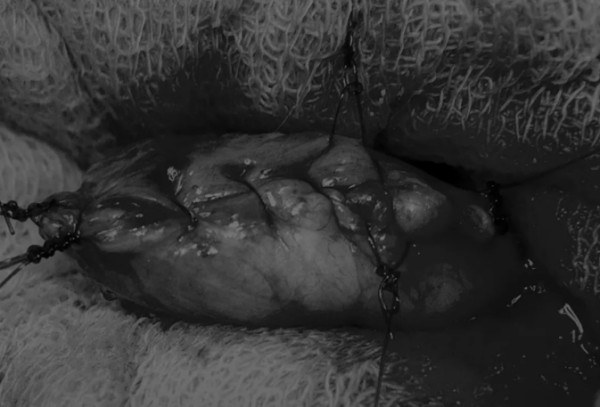

在中线开腹手术后,确定膀胱,将其取出并隔离(图1)。为了使膀胱持续暴露,可在膀胱中线两侧各放置一根固定缝线(图2)。

在牵引缝线之间选择血管扩张较差的区域用手术刀切开膀胱壁(图3)。在牵引缝合线之间用手术刀在血管不良的区域做切口。切开膀胱壁后,膀胱内的手术可按手术方案实施,例如取出结石(图4)。